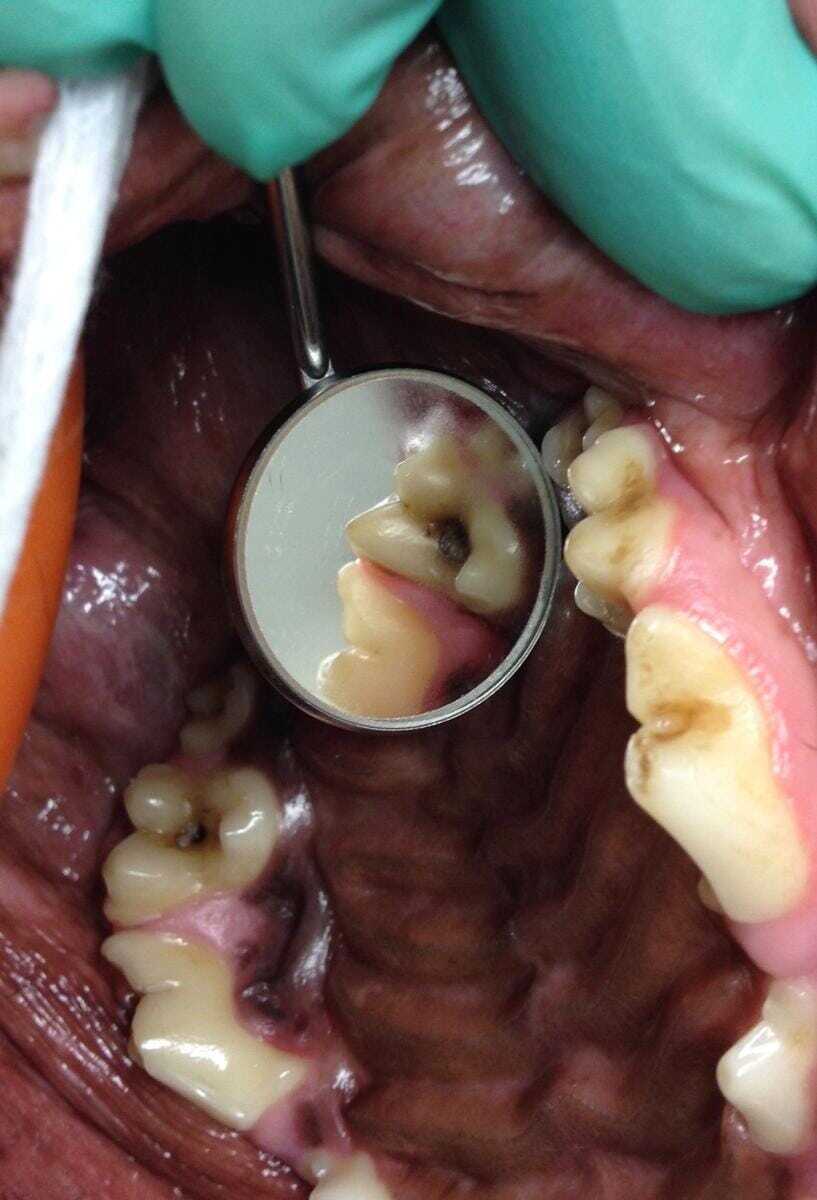

A study (Hale, 1998) found that around half of the dogs with caries lesions had bilateral and fairly symmetrically distributed lesions. It is therefore advisable to examine the entire mouth, and particularly the other molar teeth and the maxillary fourth premolar tooth, closely following the diagnosis of a caries cavity (Figure 2).